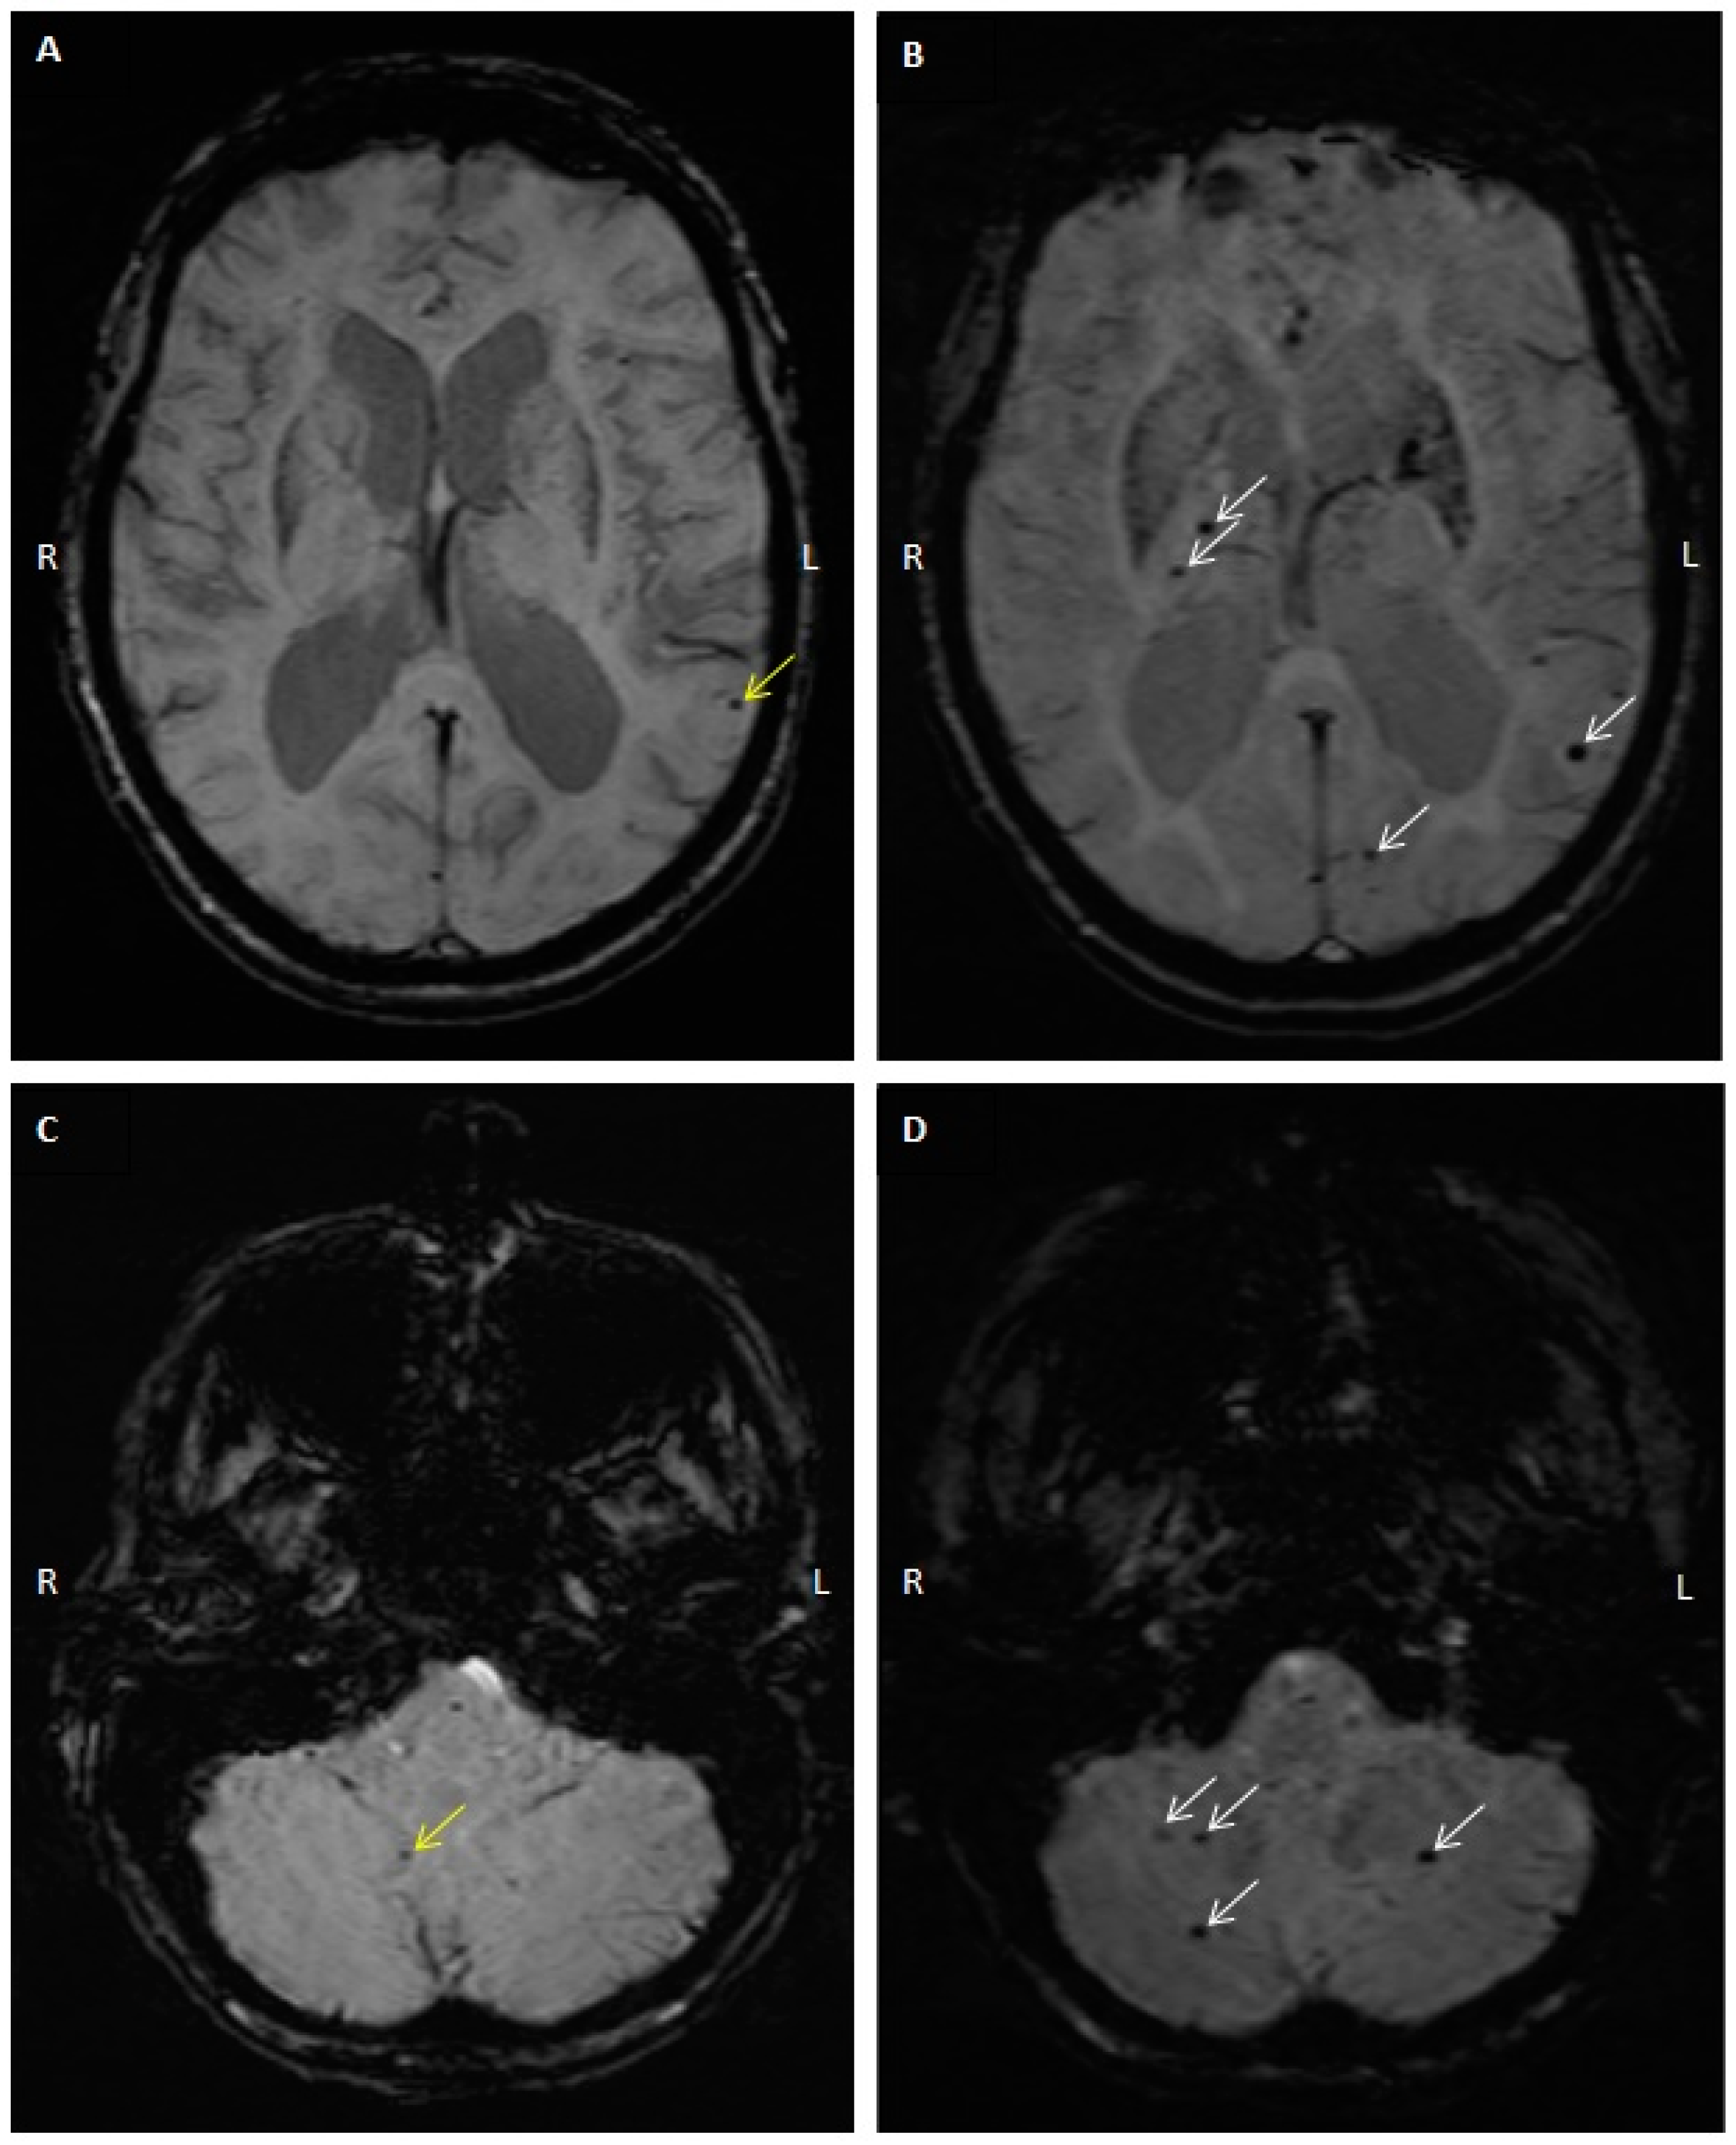

2.3. CMB Progression on Follow-Up MRI Studies

4.3. MRI and CMB Identification

4.4. Computed Tomography (CT) Interpretation and Cerebral Arterial Calcification Score